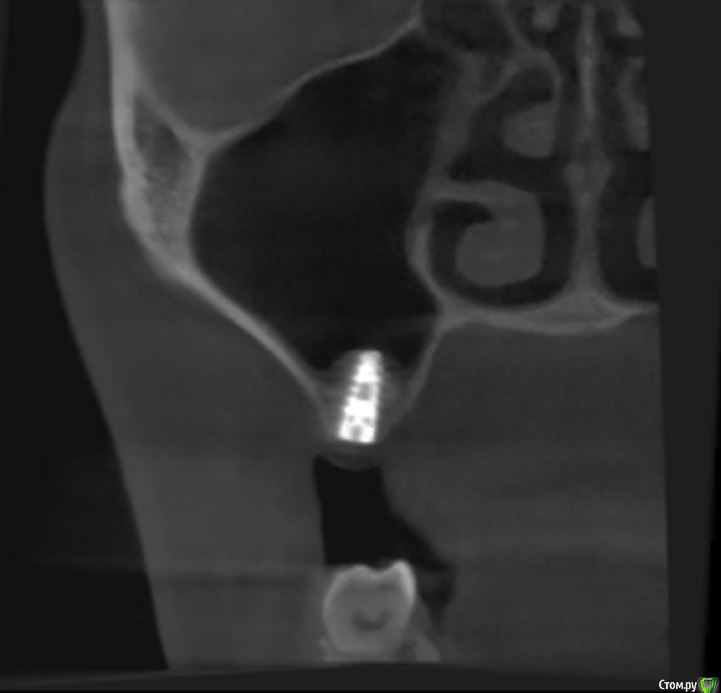

jm3300 Опубликовано 14 июля, 2016 Автор Поделиться Опубликовано 14 июля, 2016 выкладываю кт Ссылка на комментарий

умножающий печаль Опубликовано 14 июля, 2016 Поделиться Опубликовано 14 июля, 2016 Промыть пазуху через соустье, курсом. Я отправляю к ЛОРам. Антибиотикотерапия, гипосенсибилизация. Один из винтов вестибулярно без костной поддержки, на мой взгляд. 1 Ссылка на комментарий

jm3300 Опубликовано 14 июля, 2016 Автор Поделиться Опубликовано 14 июля, 2016 Промыть пазуху через соустье, курсом. Я отправляю к ЛОРам. Антибиотикотерапия, гипосенсибилизация. Один из винтов вестибулярно без костной поддержки, на мой взгляд. гайморит всё таки есть? 1 Ссылка на комментарий

red_butler Опубликовано 15 июля, 2016 Поделиться Опубликовано 15 июля, 2016 гайморит всё таки есть?Не увидел, один винт похоже на выход 1 Ссылка на комментарий

syrovovec Опубликовано 15 июля, 2016 Поделиться Опубликовано 15 июля, 2016 (изменено) Пазуха чистая, Антон, какой винт на выход не понял?Может у пац аллергия ? Изменено 15 июля, 2016 пользователем syrovovec 1 Ссылка на комментарий

kladoffka Опубликовано 15 июля, 2016 Поделиться Опубликовано 15 июля, 2016 Тоже не понял, вроде все хорошо стоят. Главное слизистые то в покое. 1 Ссылка на комментарий

умножающий печаль Опубликовано 15 июля, 2016 Поделиться Опубликовано 15 июля, 2016 (изменено) гайморит всё таки есть?Судя по симптоматике, которую вы представили, есть. На снимке признаки могут запаздывать, ежели процесс острый, хотя снижение пневматизации должно быть заметно. Я на мониторе не разглядел. Рентген всего лишь доп. метод обследования. Диагноз ставит врач, то есть вы, сопоставив клинику и доп.методы.З.Ы. Я не думаю, что в вашем случае причина гайморита имплантация. Временной интервал слишком велик. Изменено 15 июля, 2016 пользователем умножающий печаль 1 Ссылка на комментарий